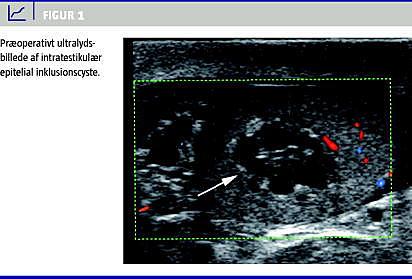

Denne sygehistorie omhandler en 22-årig mand, der ikke tidligere havde fejlet noget ved testiklerne og ikke været udsat for traume. Tilfældigt bemærkede han en forandring ved højre testikel. Egen læge henviste til ultralydsskanning af scrotum. Ved ultralydsundersøgelse fandt man i højre testikel kaudalt en centralt beliggende, afrundet, velafgrænset proces på 8 × 10 × 13 mm. Processen var primært hypoekkoisk og i mindre grad isoekkoisk i forhold til det normale testikelparenkym. Der var hyperekkoisk signal i periferien af processen mod det normale testikelparenkym. Dopplerflow viste kun normal vaskularisering af testiklen, der var intet Dopplersignal i den intratestikulære proces. Den øvrige del af højre testikel og modsatte testikel samt begge bitestikler fremstod normale, men man fandt forandringen malignitetssuspekt (Figur 1 ).